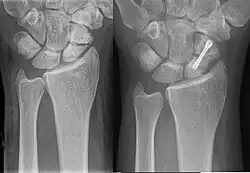

- fixation en chirurgie ambulatoire par technique percutanée,

- vissage en chirurgie classique à ciel ouvert.

Les techniques applicables dépendent du type de fracture et de sa localisation sur l'os. Pour les fractures non déplacées, principalement celles du corps du scaphoïde, la technique percutanée tend à se développer. Elle s'opère sous anesthésie locale, sans hospitalisation du patient, et dure environ 20 à 30 minutes. Ses résultats sont excellents, et la durée d'immobilisation consécutive est réduite à environ deux semaines (contre 8 à 12 semaines sans intervention). Toutefois, un traitement par immobilisation, dans les formes médiales, avec contrôle radiologique et intervention chirurgicale s'il n' y a pas de signe de consolidation, expose à moins de complications qu'une chirurgie immédiate, avec un résultat fonctionnel aussi bon[10].